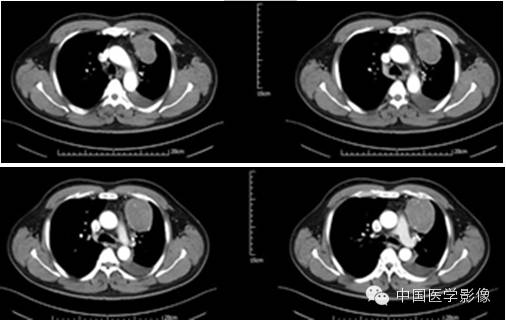

CT、MRI表现

SFT影像表现具有以下特征:

1.外形及囊变坏死:良性SFT一般为边界清晰的单发肿块无分叶或浅分叶,肿瘤大多呈实性,囊变坏死区较小。恶性SFT一般为囊实性或囊性为主肿块呈分叶状坏死范围广泛。

2.密度或信号特点:肿瘤实性部分CT表现为软组织密度,囊变坏死区呈低密度。位于胸腔的SFT尽管体积巨大,但密度相对均匀,坏死少见且范围多较小。良性肿瘤坏死少见,恶性肿瘤不规则坏死区相对多见。腹部SFT都有不同程度的坏死囊变和钙化。MRI除了能够提供明确肿瘤的确切部位及累及范围外,对于明确肿瘤的组成成分具有重要价值。MR信号改变与肿瘤的组织学特征密切相关,其内成熟的纤维组织在T1WIT2WI序列上均呈低信号,而肿瘤细胞及血管聚集区则呈等T1长T2信号,因此T1WI一般为等信号或低信号T2WI多为混杂信号。文献认为T2WI低信号对于本病诊断具有重要价值。

3.包膜:良性孤立性纤维性肿瘤多具有明显的包膜,文献报道包膜出现率约50%。包膜出现可能与肿瘤缓慢生长过程中对周围正常组织缓慢压迫有关。

4.铸型生长:由于良性SFT生长缓慢,发生于胸膜腔的孤立性纤维性肿瘤常呈斜圆锥体状,铸型镶嵌于肋膈角。此征象的出现与病灶生长时间及部位密切相关。

5.钙化:少见,文献报道部分病灶内可发生斑点、斑片状钙化,常发生在较大的肿瘤,可能与肿瘤坏死有关。

6.增强扫描:SFT为富血供肿瘤,增强扫描呈肿瘤实性部分呈地图样明显强化、延迟扫描进一步强化是SFT的主要特征。病灶实性部分显著强化与镜下血管外皮瘤样分布区及细胞密集区有关,而肿瘤内部坏死囊变区不强化。此外,细胞稀疏区与胶原纤维束玻璃样变区域强化相对较弱,因此形成地图样不均匀强化表现。持续性强化的模式可能与病灶内胶原纤维缓慢强化有关,还可能与黏液样变及细胞疏松排列导致细胞外间隙扩大对比剂在细胞外间隙内进行性聚集有关,因此动态扫描对于本病的诊断具有重要价值。

7.肿瘤继发性改变:胸腔积液,邻近肺组织受压移位、不张,呈“帽状”实变。可伴有周边骨质破坏及溶骨改变。